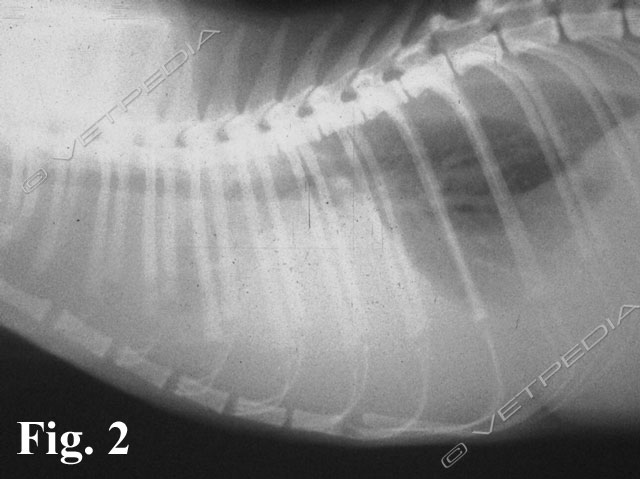

{{/_source.additionalInfo}}La Peritonite infettiva felina (Feline Infectious Peritonitis, FIP) è ritenuta la principale causa di mortalità di natura infettiva del gatto ed è una conseguenza inusuale dell’infezione sostenuta da un virus denominato Coronavirus Felino (FcoV); la maggior parte dei gatti che entrano in contatto con il virus rimane infatti asintomatica.